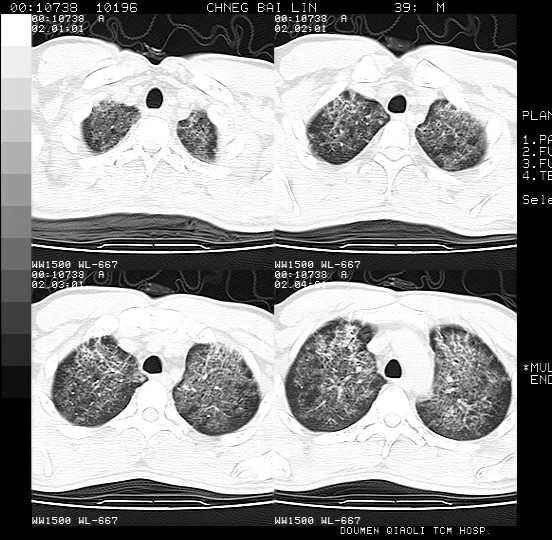

男,39岁。10天前自觉感冒,曾输液一次内容不详曾有吸毒史。现有咳嗽、咳痰胸闷。

双肺弥漫性网状、磨玻璃样病灶,边界不清。有吸毒史。首先考虑机遇性肺部感染。

两肺弥漫间质改变,考虑1、特发性肺间质纤维化。2、间质性肺炎。

两肺弥漫分布的网状毛玻璃状阴影,边缘模糊不清,纵隔未见明显淋巴结肿大

诊断:机遇性肺部感染

鉴别诊断:1特发性肺纤维化,主要部位在两肺下叶胸膜下网状,毛玻璃状及蜂窝状阴影,临近胸膜增厚,该病征象不太符合